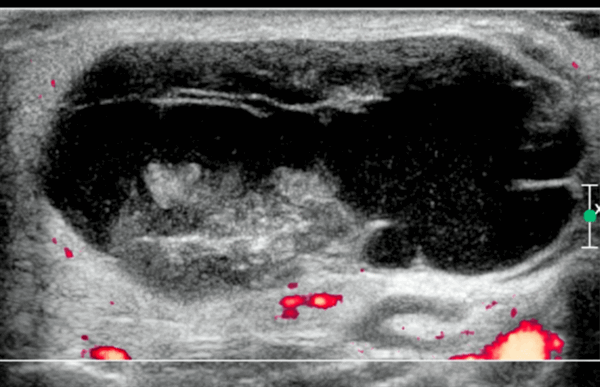

- Цветной допплер: видные внутропухолевые (при небольших солидных опухолях) и перегородочные (могут поражать) сосуды.

Опухоль Уортина считается следующей по своей распространенности доброкачественной опухолью слюнных желез на УЗИ (5-10% всех доброкачественных новообразований). Она чаще всего возникает у мужчин между пятой и шестой декадами жизни. Связь между курением и развитием опухоли Уортина была доказана. Опухоль на ульразвуковом сканировании обычно одиночная, односторонняя, и медленно растет. В примерно от 10 до 60% случаев, опухоли могут происходить с двух сторон или мкльтифокально, иногда она растет несинхронно в разных железах и проявляется клинически в разное время.

Спорадически, эпителиальный компонент опухоль Уортина может подвергнуться злокачественной трансформации. На УЗИ опухоль выглядит в виде овальной формы, гипоэхогена, с четко определенными границами и часто содержит множество анэхогенных зон. Образование при ЦДК часто гиперваскуляризировано.